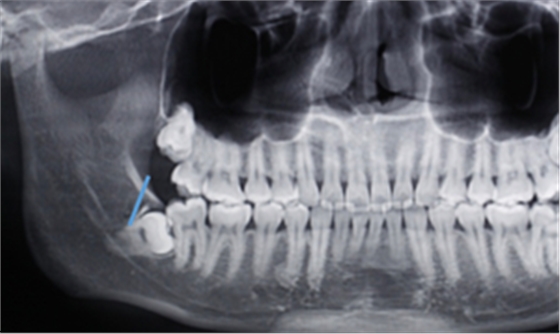

第二:充分暴露牙體組織后,沿47牙長(zhǎng)軸方向?qū)?8進(jìn)行分冠,分冠線如下:

第三:分冠后近中牙體組織若無(wú)法順利脫位,可進(jìn)一步將近中牙冠分為頰舌兩部分,依次脫位。